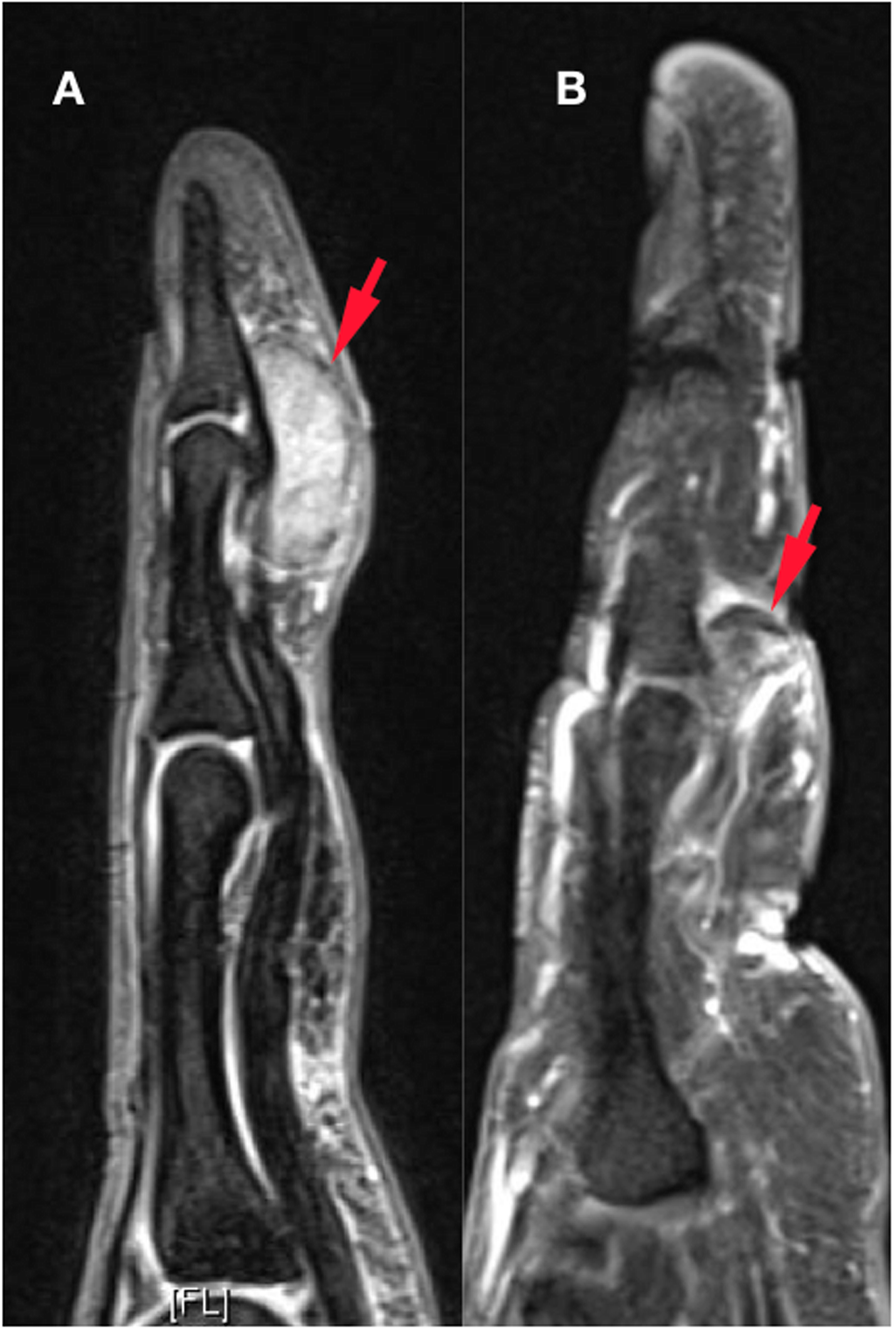

t(1;2)-Positive Localized Tenosynovial Giant Cell Tumor With Bone Invasion | In Vivo